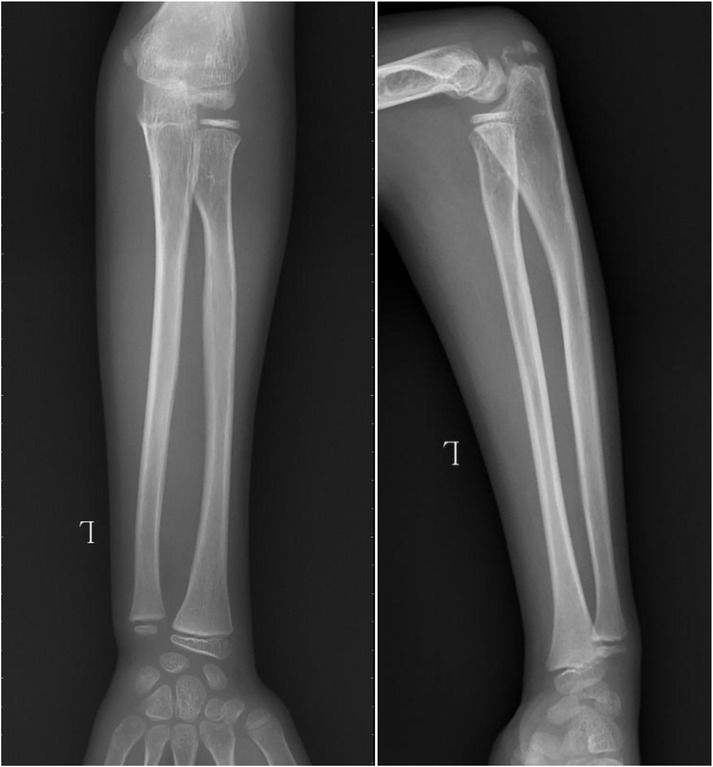

Objective: To investigate and analyze the application value of elbow arthrography in the treatment of chronic radial head dislocation in children. Methods: From January 2014 to January 2017, 15 children with chronic anterior radial head dislocation were treated (11 boys, 4 girls; average age 9 years, range 3-11 years). Intraoperative elbow arthrography was performed to assess the position of the radial head relative to the joint capsule. The nature of the dislocation was confirmed by opening the joint capsule to directly observe the relationship between the radial head and capitellum, as well as the morphology of the radial head. Reduction of the radial head was achieved via proximal ulnar osteotomy, and fixation was performed using a plate and screws with or without Kirschner wires (K-wires). Results: Elbow arthrography showed the radial head was located within the joint capsule in 12 cases and outside the capsule in 3 cases. Among the cases: All 8 congenital dislocations had the radial head within the joint capsule. Of the 7 traumatic dislocations, 4 had the radial head within the capsule and 3 outside. Direct inspection after capsulotomy confirmed the arthrography findings and revealed characteristic morphological differences. In congenital dislocations, there was no scar tissue between the radial head and capitellum, and the radial head fovea was shallow and flat. In traumatic dislocations, obvious scar tissue was present between the radial head and capitellum, and the radial head fovea was distinct. Follow-up ranged from 9 months to 4 years (average 2 years 5 months). Postoperative radiographs showed no cases of radial head re-dislocation or subluxation. Postoperative elbow range of motion improved in all patients, with no reports of pain or functional instability. Conclusion: Elbow arthrography serves as a valuable adjunct for differentiating between congenital and traumatic radial head dislocations, thereby informing both surgical strategy and the decision for supplemental fixation. When stable bony alignment is achieved, proximal ulnar osteotomy without annular ligament reconstruction represents an effective management strategy for chronic radial head dislocation in children.